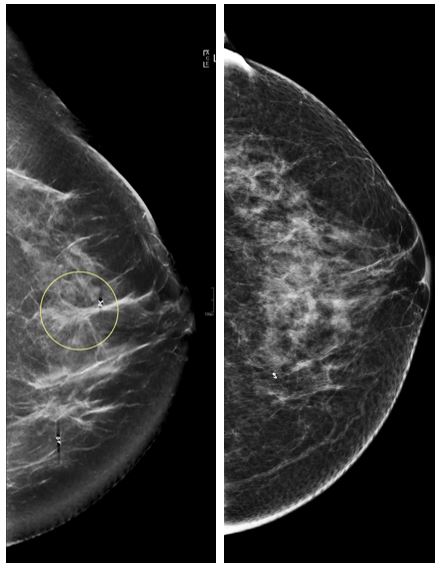

Digital breast tomosynthesis, also known as DBT, is a further evolution of digital mammography in which a series of low-dose projection images of the breast are obtained at different angles. According to a recent, multicenter study, published in JAMA Oncology in February 2019, it can lead to better breast cancer detection and fewer false-positive recalls compared to digital mammography.

At UCSF Radiology, we know that conventional mammography is certainly a life-saving tool, and DBT represents a significant step forward. It has the potential to detect some cancers at screening that are not visible by conventional mammography, the majority of which are invasive cancers. Additionally, DBT has been shown to reduce false-positive callbacks at screening. For patients referred for a breast symptom or workup of an imaging finding, DBT may enable more definitive and efficient characterization of breast abnormalities. Findings from this study further support these ideas.